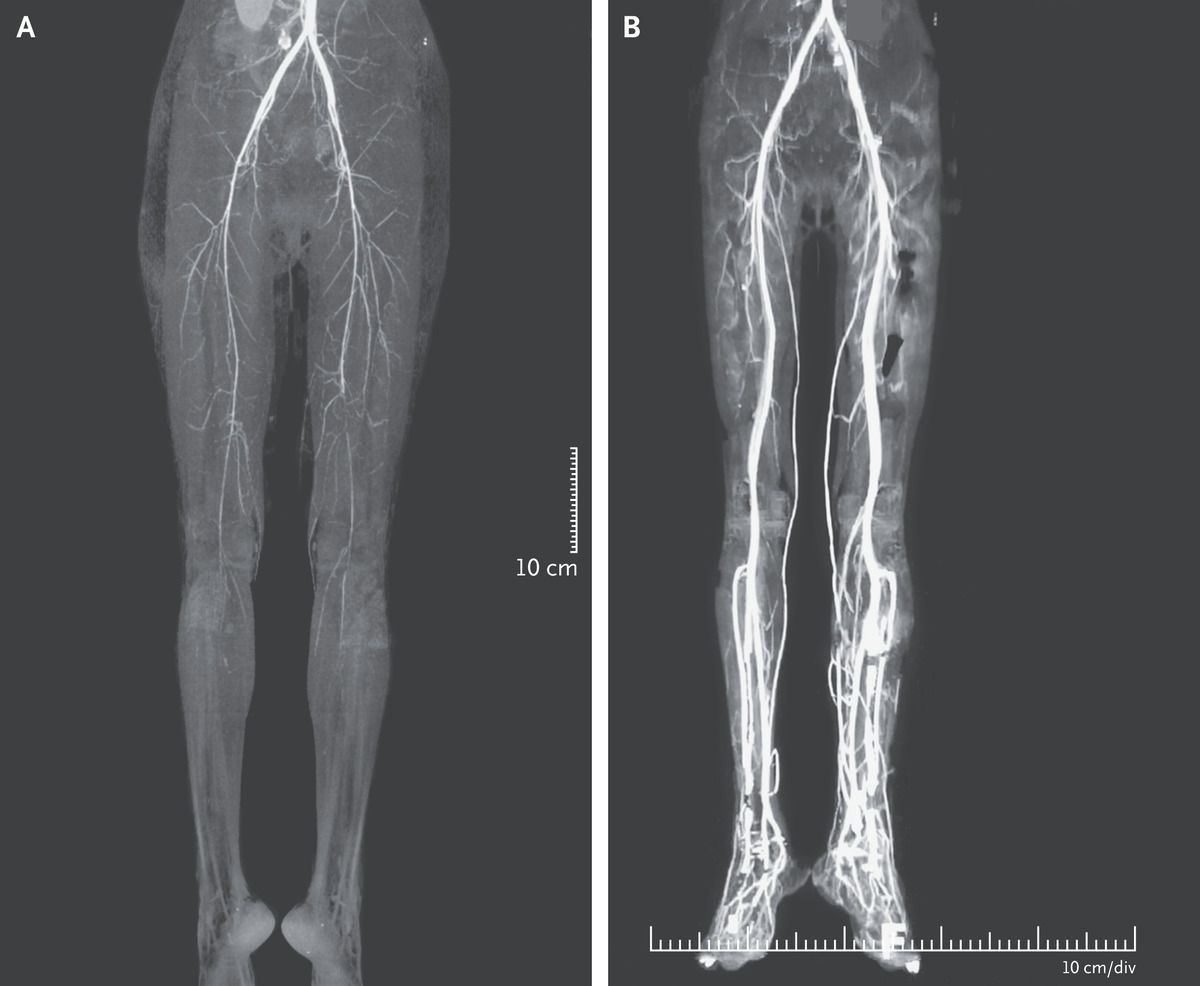

A 24-year-old woman presented to the outpatient clinic with a 2-day history of severe, burning leg pain. She had a history of congenital infection with the human immunodeficiency virus, for which she was taking tenofovir, emtricitabine, and lopinavir–ritonavir. Four days before presentation she had also started taking ergotamine twice daily for a migraine headache. The pain in the legs extended from the toes to the midthigh and was accompanied by discoloration of the feet and difficulty walking. On examination, both legs were cold, with nonpalpable popliteal and dorsalis pedis pulses. Computed tomographic (CT) angiography revealed diffuse, symmetric, luminal narrowing of the arteries below the external iliac artery in both legs (Panel A). A diagnosis of ergotism was suspected. Ritonavir inhibits the enzyme CYP3A4, leading to increased serum levels of ergotamine and thereby causing vasospastic limb ischemia. Treatment with intravenous prostaglandin and unfractionated heparin was initiated. The pain subsided, and patient’s legs became warmer, but she underwent amputation of the left second toe owing to gangrene. A repeat CT angiogram obtained 2 weeks after presentation showed improved perfusion in both legs (Panel B).